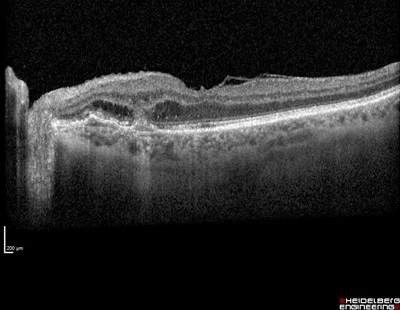

An 84yr old lady was being treated for subretinal new vessel in the right eye. Treatment was progressing well and the vision was 6/7.5-1 in the right eye and 6/7.5-2 in the left, having had previous cataract surgery. An incidental finding was noticed in the asymptomatic left eye on fundal examination.

OCT shows a peripapillary sub retinal new vessel-SRNV. Initial examination could confuse this with a choroidal naevus or melanoma.

Careful examination of the photo shows some streaky lipid supertemporal to the macula indicating chronic fluid leakage and membrane activity.

The OCT shows a SRNV with outer retinal fluid and a sub retinal pigment epithelium SRNV expanding into the subretinal space.